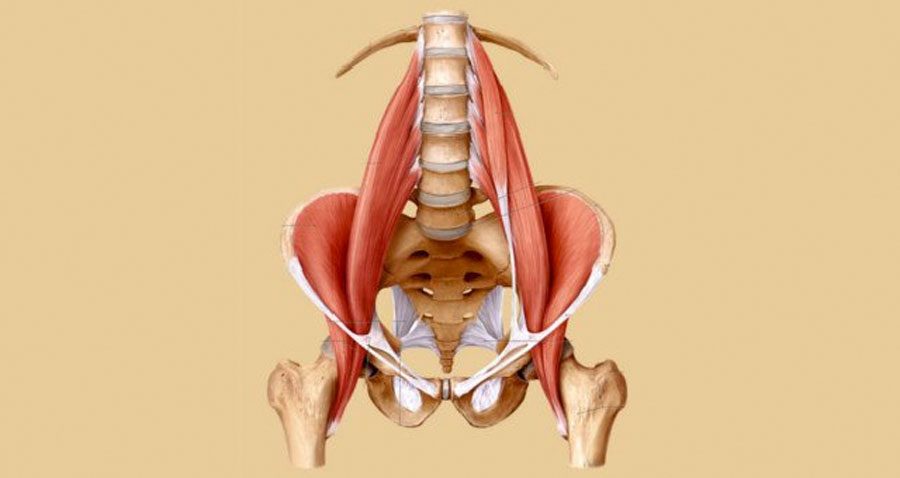

¿Dónde está el psoas?

El psoas es el músculo principal asociado con la estabilidad física. Se extiende desde las piernas hasta la columna vertebral y es el único músculo que conecta las piernas con la columna vertebral. El músculo comienza en la vértebra T12, continua por las cinco vértebras lumbares, antes de conectar a la parte superior del hueso del muslo (fémur).